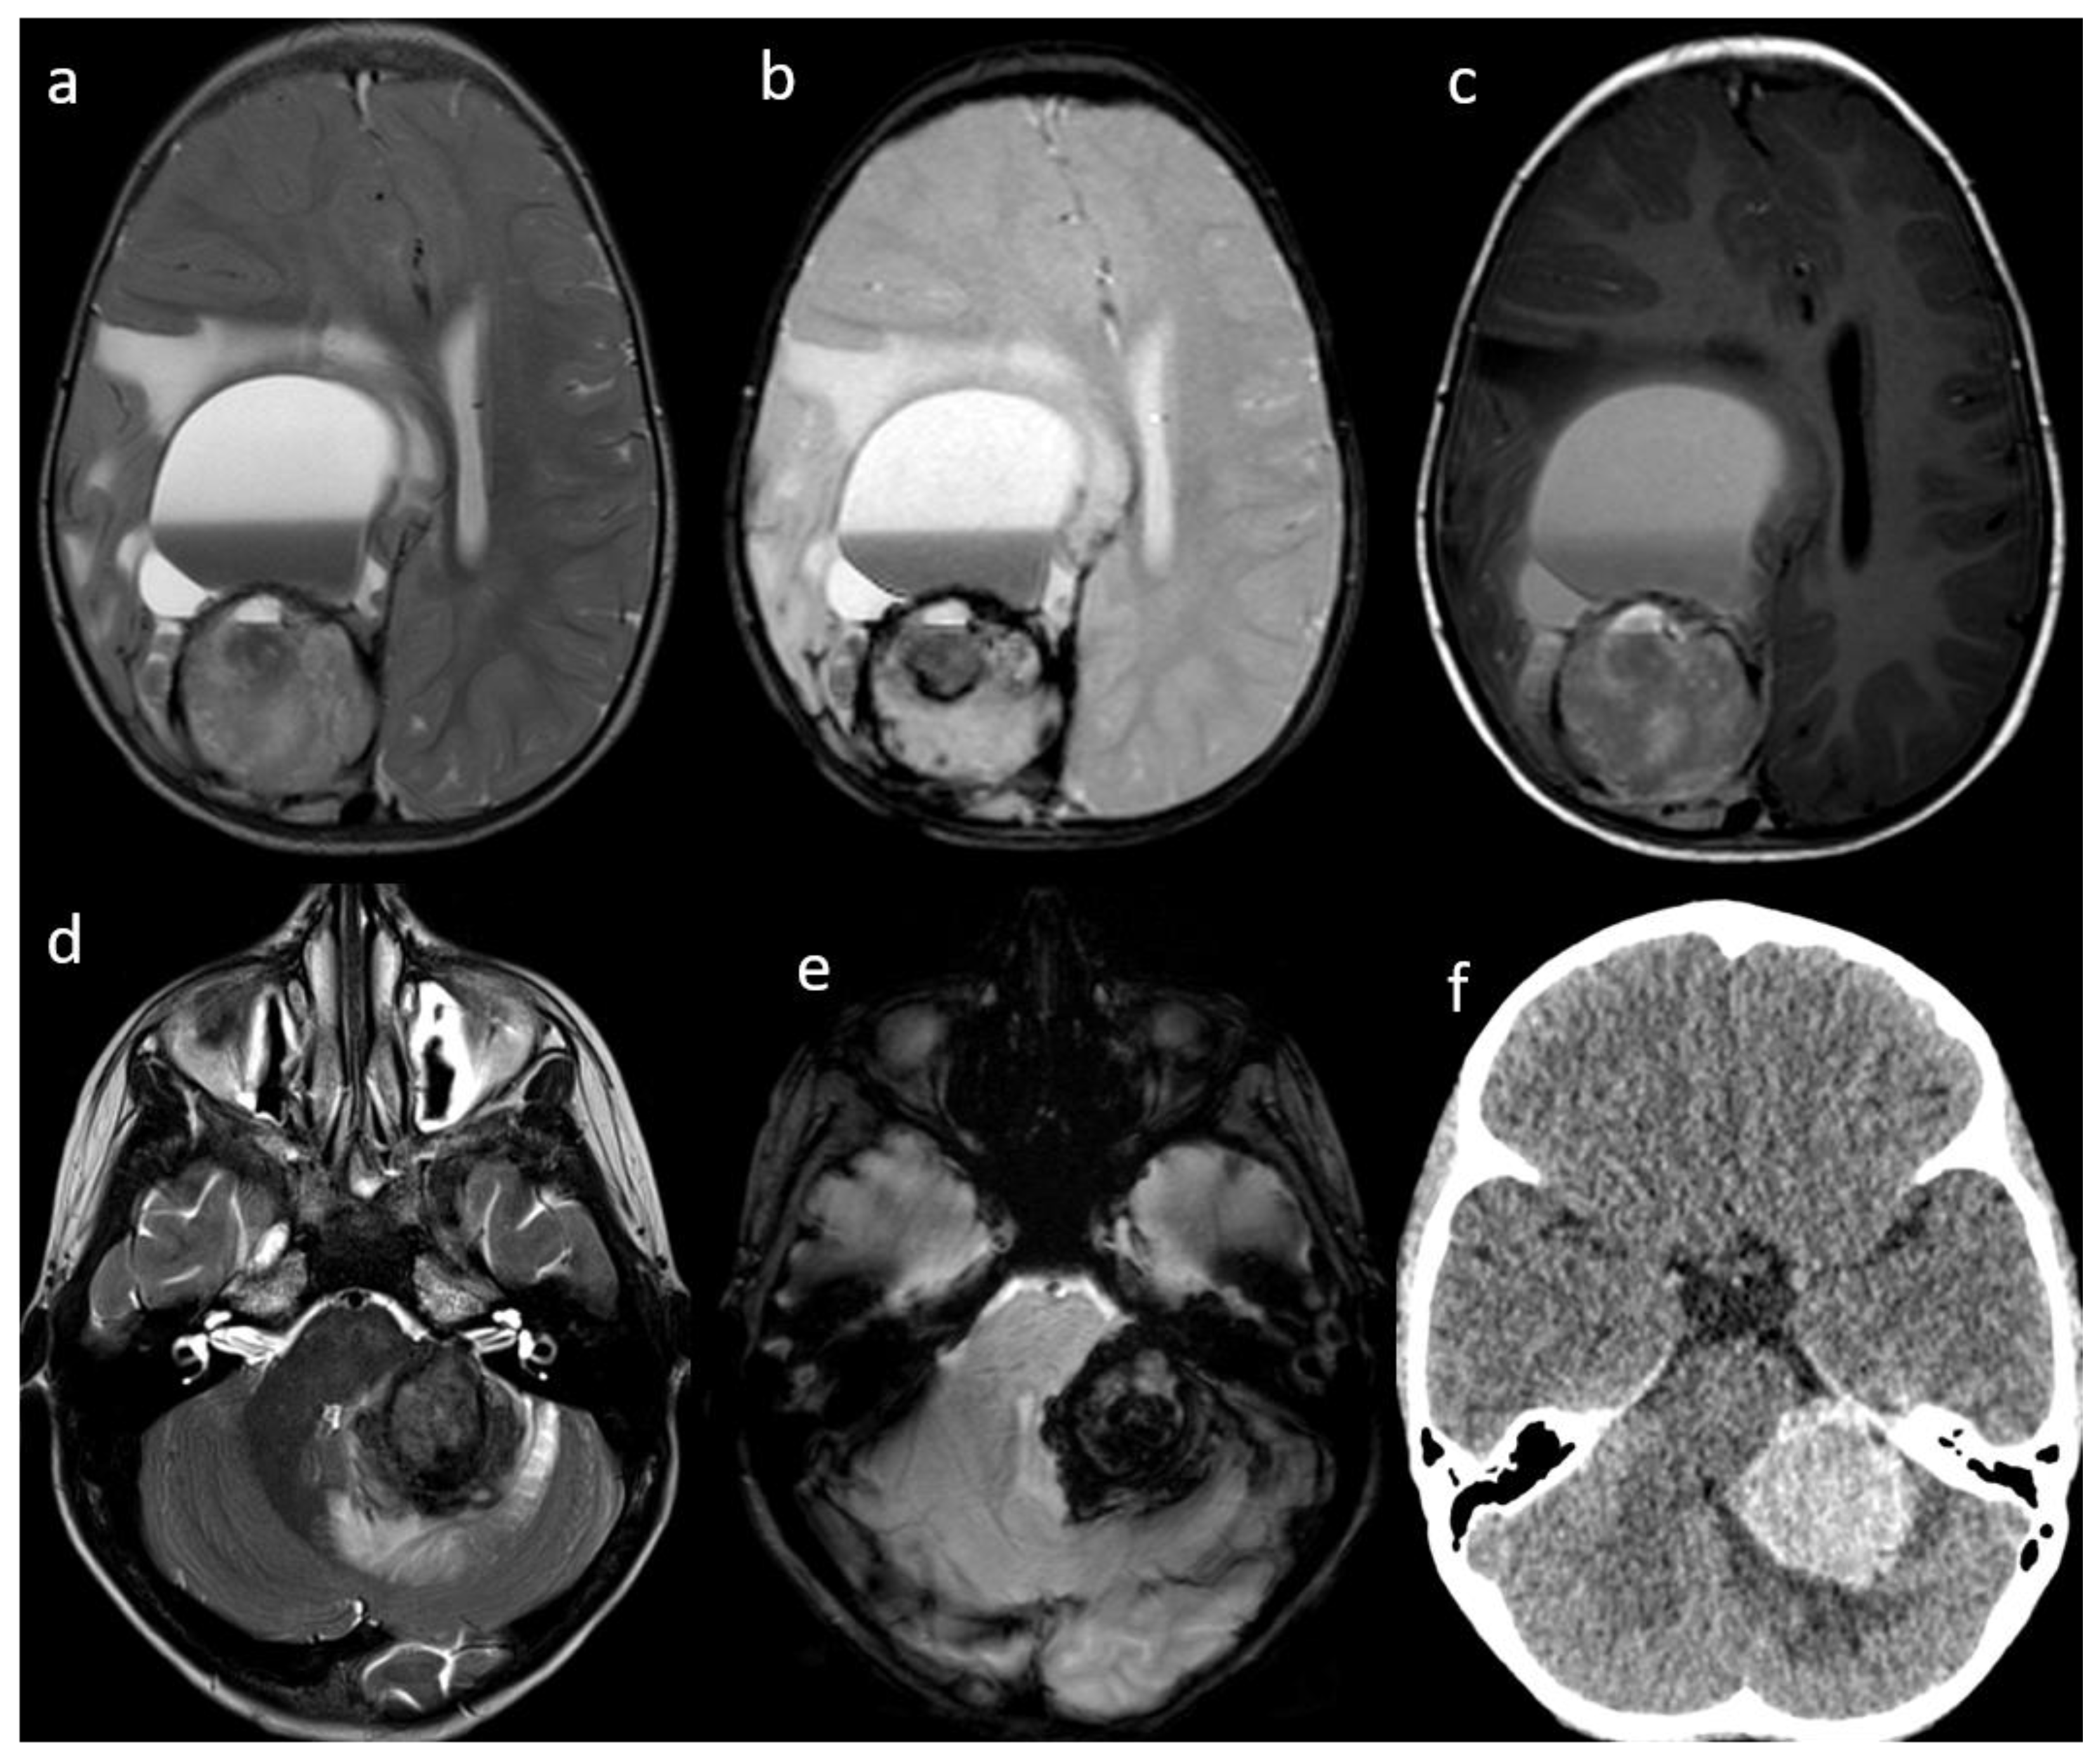

| 1 | brain parenchyma | right cerebral hemisphere | 1 | 90 × 60 × 50 | CT MRI | yes | Yes | yes | yes | yes | N/A | N/A | performed after surgery |